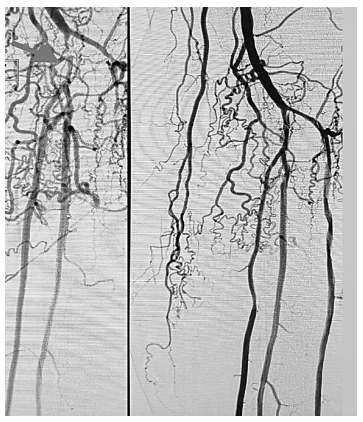

A imagem acima corresponde a uma angiografia digital demonstrando o pré e pós procedimento de angioplastia de membro inferior esquerdo. Qual é a estrutura anatômica assinalada em seta?